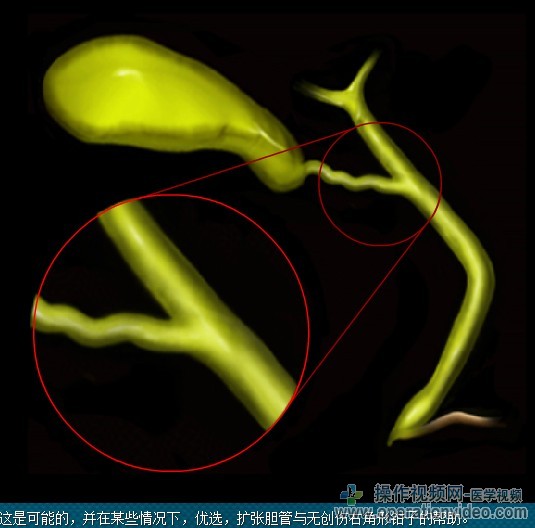

它是强制性的,以确认已完全清除,CBD。这可能与胆道镜,胆道造影或超声检查。

“生物多样性公约”的探讨乳头。以上,内镜下胆管和“生物多样性公约”结探索是困难的。在怀疑结石位于近侧的情况下,有,胆管造影应进行。

通过胆囊管当直接提取的石头的大小是不可能的,因为,它可能有必要使沿胆囊管的纵向切口的突起的上在石头上。石头然后可以提取使用无创伤抓取(见视频)。

在扩张胆管的箱子,一个剪辑的长度可能是不够的,它可能是必要诉诸到绑带(预制的循环或体内缝合)为了确保胆囊管有没有泄漏。